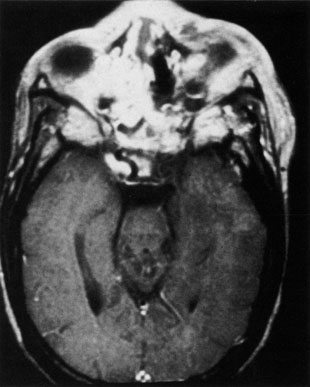

Rhinocerebral mucormycosis originates as a rhinitis, parapharyngitis, or sinusitis, and spreads by invasion of blood vessel walls, causing a necrotizing vasculitis with thrombosis of the vascular lumina and resultant infarction. The patient typically presents with unilateral orbital apex syndrome, including severe pain, visual loss, total ophthalmoplegia, corneal anesthesia, and multiple cranial nerve palsies.127 Orbital cellulitis presenting with early visual loss is one of the hallmarks of mucormycosis.72 Gangrene may occur of external periorbital tissues as well as of the hard palate and nose, and eschar-like crusting may be observed within the nose or on the hard palate (Fig. 23). Obstruction of the central retinal artery, ciliary arteries, and choroidal circulation can also be seen.124,125 Brain damage may occur because of spread of infection or infarction or occlusion of affected intracranial vessels.72

Fig. 23. Mucormycosis of the right ethmoidal sinus, with right orbital subperiosteal abscess formation. A. T1-weighted axial image. B. T2-weighted image. Note brain abscess.

CT shows sinusitis with or without bone destruction and is indistinguishable from other causes of orbital cellulitis.128 MRI may show carotid narrowing, occlusion, and absent flow in the superior ophthalmic vein (Fig. 24).72